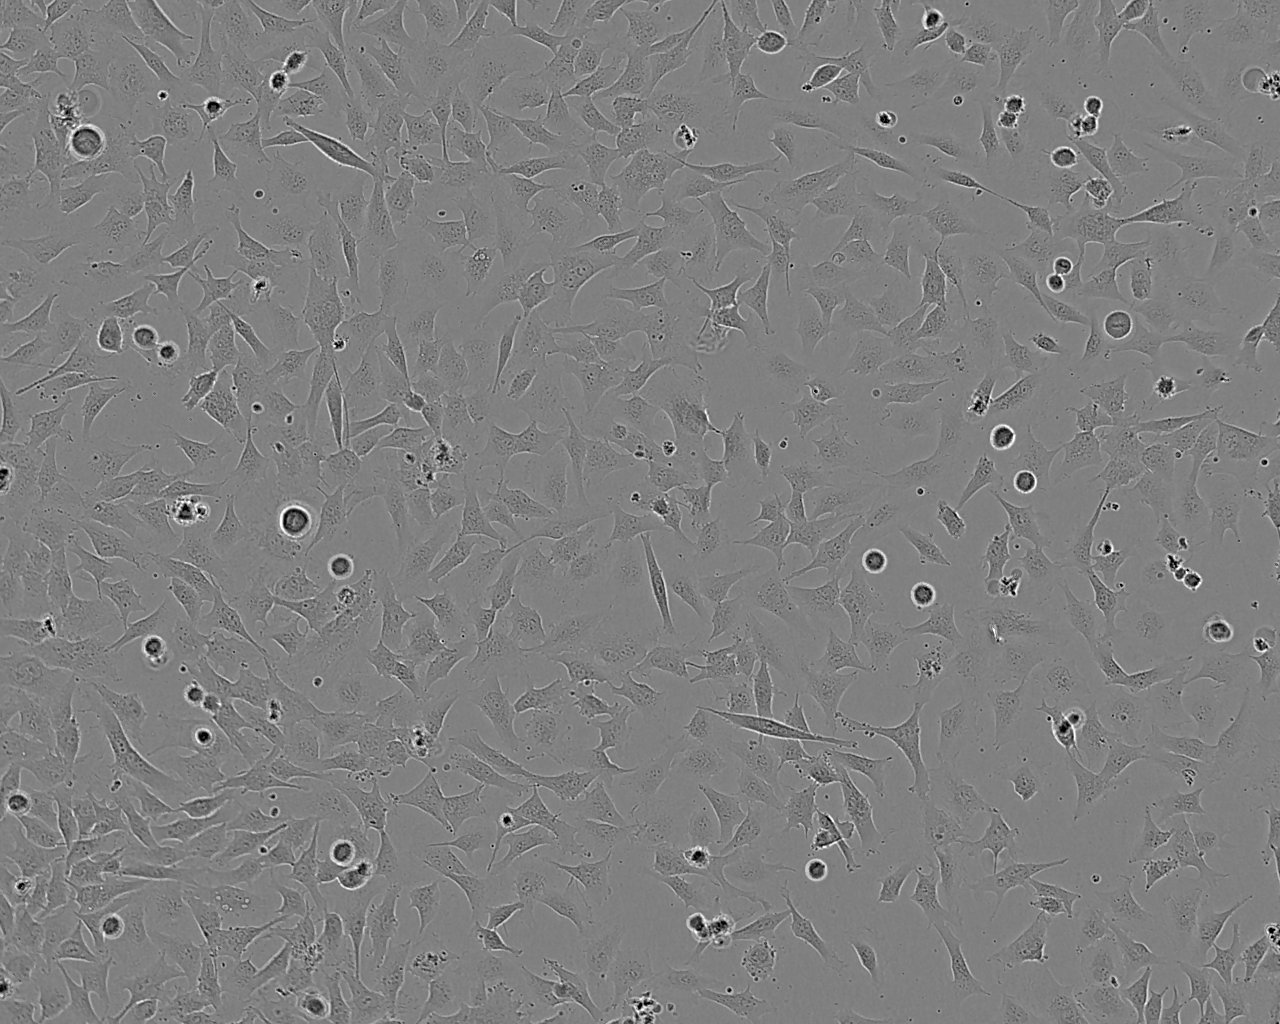

Derived from a subcutaneous nodule of a tumour from a 14-year-old male. Cells display remarkable blebbing.COLO 800 and COLO 794 (ECACC Catalogue number 94072237) were both derived from the same 14 year old male This has been confirmed by STR profiling.

Fibroblastic

Adherent